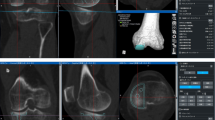

In total, 88 patients with medial osteoarthritis who underwent CR-TKA using a navigation system (Precision Knee Navigation software version 4.0; Stryker, Kalamazoo, MI, USA) in our hospital were enrolled in this retrospective study. Those with valgus alignment knees, existing inflammatory arthritis, and incomplete rotational laxity data were excluded to unify the conditions of the patients.

Overall, 63 knees of 55 patients with a mean age of 72.4 ± 8.1 years (range: 45–85 years) were enrolled in the study. The average pre-operative hip–knee–ankle angle was 10.6 ± 5.8° in varus knees. The implants used were NexGen CR-Flex, Persona CR (Zimmer, Warsaw, IN, USA, n = 37), and FINE Total Knee System (Nakashima Medical, Okayama, Japan, n = 26). Further patient characteristics are listed in Table 1. The patients were divided into two groups according to the TKA design concept. NexGen CR-Flex and Persona CR, which induce kinematics to the inherent restraint of implants by adopting the symmetrical surface design of neutral joint-line obliquity between the femoral condyle and the tibial insert, were classified as group S. On the other hand, the anatomical approach that prioritises the kinematics inherent in soft tissues, as the FINE Total Knee System has an asymmetrical design with 3° of joint line obliquity on the insert of the coronal alignment to build in anatomical elements, was classified as group A (Fig. 1) [31, 33]. Both group models adopt multi-radius designs for the femoral component. Meanwhile, there are differences in the radius size between the medial and lateral condyle of group A to reproduce the anatomical joint line. The medial parapatellar approach and measured resection technique were used for all knees. Femoral and tibial joints were resected by mechanical alignment.

The femoral rotational axis was defined as being perpendicular to the Whiteside line. The tibial rotational axis was set parallel to the line connecting one-third of the tibial tubercle to the centre of the cut surface. Anchoring pins with an infrared signal transducer were fixed into the femur and tibia as reference points, and the joint capsule was temporarily closed with four strands of suture after registration. The investigator gently applied physiologically allowable maximal manual internal and external rotation stress to the knee without angular acceleration, and the mechanical femoral–tibial rotational angle was measured automatically by the navigation system at 30°, 45°, 60°, and 90° of knee flexion. The measurements obtained directly following joint-capsule closure, with the presence of osteophytes, soft tissues, meniscus, and the cruciate ligaments, were defined as the pre-operative record. The articular surfaces of the distal femur and the proximal tibia were resected using the navigation-assisted measured resection technique. The largest sized components without both anteroposterior and mediolateral overhang were selected, after utilising the femoral-sizing guide and tibial-sizing plate. After trial components were placed, the medial–lateral balance of the knee was assessed throughout ROM. When the soft tissue balance was inappropriate, a minimal-released stepped adjustment was applied for accurate ligament balance as necessary: the release of medial collateral ligament, posterior knee capsule or PCL, or bone additional resection.